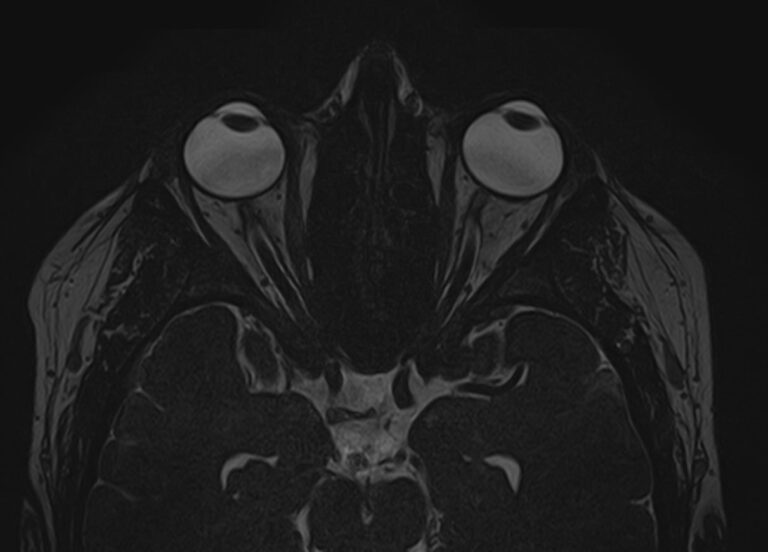

При необходимости визуализации всех отделов головного мозга с прицельным исследованием орбитальной области в клинике «Доступная медицина» проводится комплексное исследование — МРТ головного мозга + МРТ орбит. Это два отдельных исследования, каждое из которых имеет свой протокол сканирования, но при этом они могут проводиться в одно время.

Глазницы (орбиты) — это углубления в лицевом черепе, в которых расположены глазные яблоки, жировая клетчатка, мышцы глаза со связочным аппаратом, слезные железы, зрительные нервы. Волокна зрительных нервов проходят через анатомические отверстия глазниц в полость черепа, затем после частичного перекреста направляются к подкорковым зрительным анализаторам, а от них нервные окончания идут к зрительным центрам коры головного мозга в затылочной области.

Зрительный путь достаточно длинный и на всем его протяжении могут возникнуть патологические процессы, которые становятся причиной нарушения зрения. Иногда это связано с патологией другой области головного мозга, например, опухолью гипофиза. Поэтому в ряде случаев необходимо провести одновременное сканирование глазных орбит и головного мозга, чтобы выяснить, на каком отрезке пути произошло поражение, которое привело к снижению зрения.

Что покажет МРТ головного мозга + МРТ орбит

При обследовании головного мозга и орбит можно выявить:

• Опухоли орбит, воспалительные изменения глазного яблока и его придатков.

• Атрофию зрительного нерва, отслойку сетчатки, инородные тела орбитальной области.

• Объемные образования головного мозга или гематомы, сдавливающие зрительные пути.

• Очаги ишемического инсульта, кровоизлияние после геморрагического инсульта в подкорковых структурах, где расположены зрительные анализаторы, либо в затылочных долях, где находится зрительная кора головного мозга.